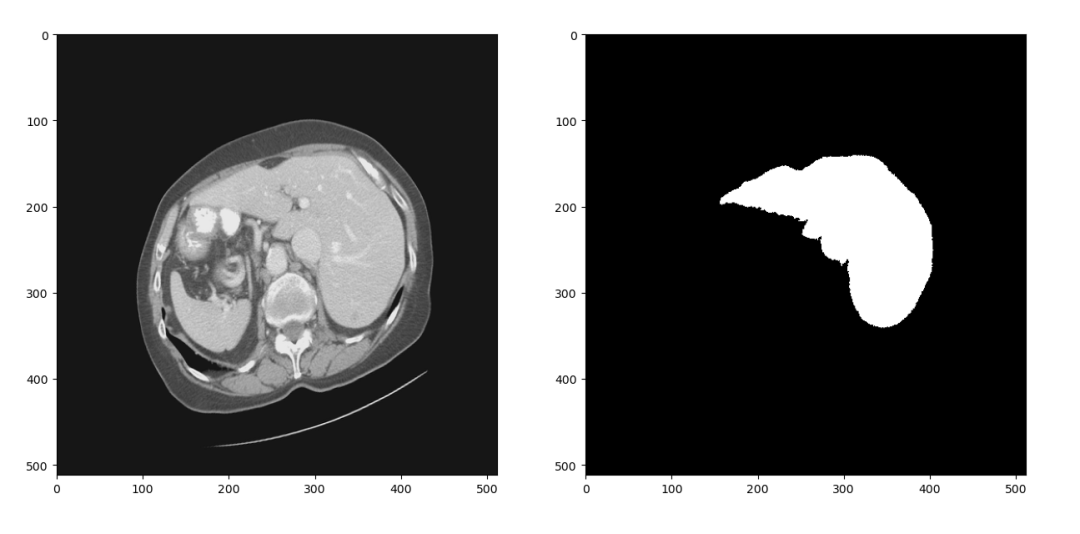

在训练深度神经网络的过程中,我们通常需要在训练集上训练多个epoch以让网络达到一个比较高的训练准确率。但是这样做又容易使网络过拟合训练集,其表现为网络在训练集上准确率很高但是测试时准确率偏低。针对这个问题有多方面的解决方案,数据增强是其中重要的一种。这个项目中我们采用的数据增强策略包括随机水平、垂直翻转、随机旋转、随机尺度缩放、随机位置裁剪和弹性形变。在项目中可以看到具体代码,图5是对图4中数据进行数据增强的结果:

图5 数据增强效果

CT图像和分割标签共同进行了左右翻转,逆时针15度旋转,0.8倍尺度缩放和弹性形变。虽然一些简单的数据增强步骤过后图像看起来没有很大区别,但是只要图像有变化对算法来说就是新的数据,结合Droupout、权重正则化等方法能较好地抑制网络过拟合,提升测试准确率。